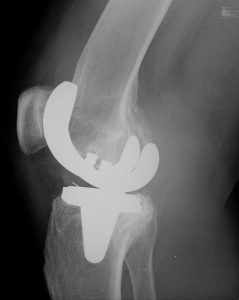

Rentgenové vyšetření břicha.Přístrojové vybavení a ukázkové snímky:

- Siemens Multix Fusion, Siemens Ysio Max a Siemens Ysio X.pree